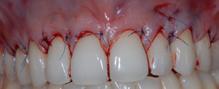

Figure 8.1.a : Situation préopératoire récessions gingivales multiples.

Figure 8.1.b : Situation en fin d’intervention après un déplacement de la gencive sur la racine, associé à une greffe de tissu conjonctif.

Figure 8.1.c : Résultat à 3 mois.